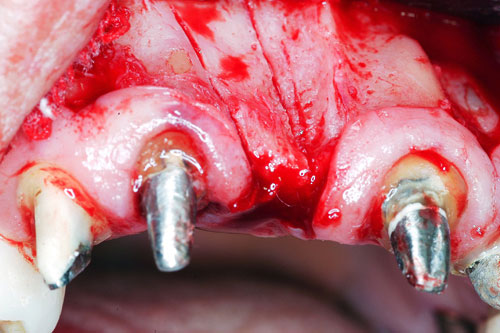

Mientras dichos movimientos ortopédicos se producen (período que supondrá otros seis meses), estudiamos los actos quirúrgicos a realizar en los cuatro implantes que pondremos. De acuerdo al estudio Desatascan realizado observamos tres situaciones diferentes: 1º-El Primer Molar Inferior Izquierdo, lo instalamos mediante Cirugía Minimamente Invasiva , con la aplicación de una Férula Quirúrgica Obtenida de los datos del scanner tratados con un programa de CMI (Cirugía Minimamente Invasiva), previa prueba en un modelo estereolitográfico, ya que la altura ósea era apenas de 9 mm. 2º- El Primer Molar Superior Derecho, se implantará mediante una ligera Elevación Atraumática (Trans alveolar) de Seno una vez logrado el espacio mesio distal necesario. 3º- El Incisivo Central Superior Derecho ausente, cuenta con un sustrato óseo prácticamente inexistente. El espesor de la tabla era de menos de 2 mm. Los caminos posibles a seguir para contar con una Rehabilitación de piezas independientes son dos: Optamos por esta segunda opción por ser menos cruenta y no necesitar de una zona dadora. Técnica esta que pondremos en práctica en dos etapas diferidas: 1º-Incisión horizontal palatinizada, incisiones peri rodetes gingivales e incisiones de descarga. Dilatación que comenzamos con dos incisiones de descarga sobre la cortical vestibular realizadas con disco. y el comienzo de la dilatación propiamente dicha mediante una hoja de bisturí, para luego seguir con un periostótomo . Recién después de alcanzada una cierta separación de la cortical vestibular de la palatina, empezamos con los dilatadores roscados. En este punto podríamos haber utilizado sin riesgos un Implante de 3,8 mm de diámetro, pero a fin de mejorar la estética del pilar emergente decidimos rellenar con material osteoconductor y osteoinductor (BiOss) y cubrir mediante membrana reabsorvible ( Bio Guide). 2º-Implantación seis meses después. Mientras se van cumpliendo los tiempos antes mencionados, y comprobamos reiteradamente la funcionalidad de la oclusión con los provisorios, tomamos impresiones definitivas y construimos primero el maxilar inferior, para definir en primer término la porción inferior de la Guía Anterior., y a nivel posterior Curvas y Microplanos. Para luego realizar los cuadrantes premolar- molar del superior: La espera de la regeneración ósea y sus tiempos pertinentes, más la espera de los tiempos de la implantación, nos obligaron a modificar las etapas del protocolo D.AT.O de manera de mantener la –D- mediante el sector superior de la GA. en provisorios, mientras fuimos resolviendo en forma definitiva los demás sectores. Ya pasados los meses necesarios para recrear un hueso adecuado en el área del Incisivo Superior Derecho, procedemos a resolver la implantación de dicha zona, observando que todo el esfuerzo dedicado al mismo había sido inútil, ya que la formación de hueso se produjo minimamente. Cuatro meses después tomamos impresiones del sector Antero Superior de la Guía Anterior, incluyendo el arrastre de un transfer . Seguimos modelando la encía con un nuevo juego de provisorios. Y se construye entonces el sector superior de la Guía Anterior. Se efectúa un control radiográfico a los 6 meses. Se ha intentado mostrar en esta Rehabilitación, que a pesar de las distintas circunstancias de cada paciente, siempre debemos tener en cuenta la necesidad de ejercer la DESOCLUSIÓN del caso como prioridad número uno, para luego perseguir la ALINEACIÓN TRIDIMENSIONAL de las arcadas y obtener así una OCLUSIÓN equilibrada. D.AT.O. ES EL PROTOCOLO QUE DEBEMOS SEGUIR EN TODA REHABILITACIÓN. BIBLIOGRAFÍA 1)William Mc Horris,B.S.,D.D.S. Oclusión. Con especial énfasis sobre :El rol funcional y parafuncional de los dientes anteriores. 2)Von Spee , Craff(Anatomista alemán, describió la curva de compensación de la articulación de molares y premolares).CURVA DE SPEE 1.89 3)Stuart,D.”Some aspects of the inervation teeth.”Procedings of Royal Society of Medicine.20:1675,19274)Muhleman,H. y Savdir,S”Tooth movility-its causes and significance”Journal of Periodontology ,36:153,Marzo ,Abril,1965. 4)Muhleman,H. Y Savdir,S”Toothmovility its causes and significance” Journal of Periodontology,36:153,marzo,abril,1965. 5-Oclusión y Diagnóstico en Rehabilitación Oral. 6-Anatomia Odontológica. 7-A contribution to the study of the movementes of the mandible. 8-Celenza F.W, Nadeskin J.F.,Oclusión.Situación actual. 9-D´Amico 10-Dawson P.E. 11-Huffman –Regenos. 12-Hobo S.-Takayama H.A. 13-Lucia V.O 14-Mc Horris. 15-Mc Horris. 16-Stuart C. 17-Vartan Veshnilian 18-Alvarez Cantoni H. AUTOR:Ratificación del Protocolo en Rehabilitación Bucal a pesar de las incidencias propias de cada caso clínico. A propósito de un caso.

Cubrimos con membrana reabsorvible.

Esperamos seis meses antes de implantar.

No obstante pudimos implantar satisfactoriamente mediante un implante de 4.2 mm. de ancho y 14 mm. de largo, con una nueva R.O.G.

El implante se encontraba perfectamente según comprobaciones radiográficas y clínicas al sondeo.